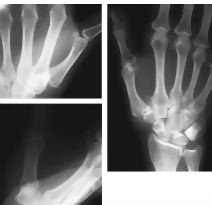

Osteoarthritis of Thumb Carpometacarpal Joint